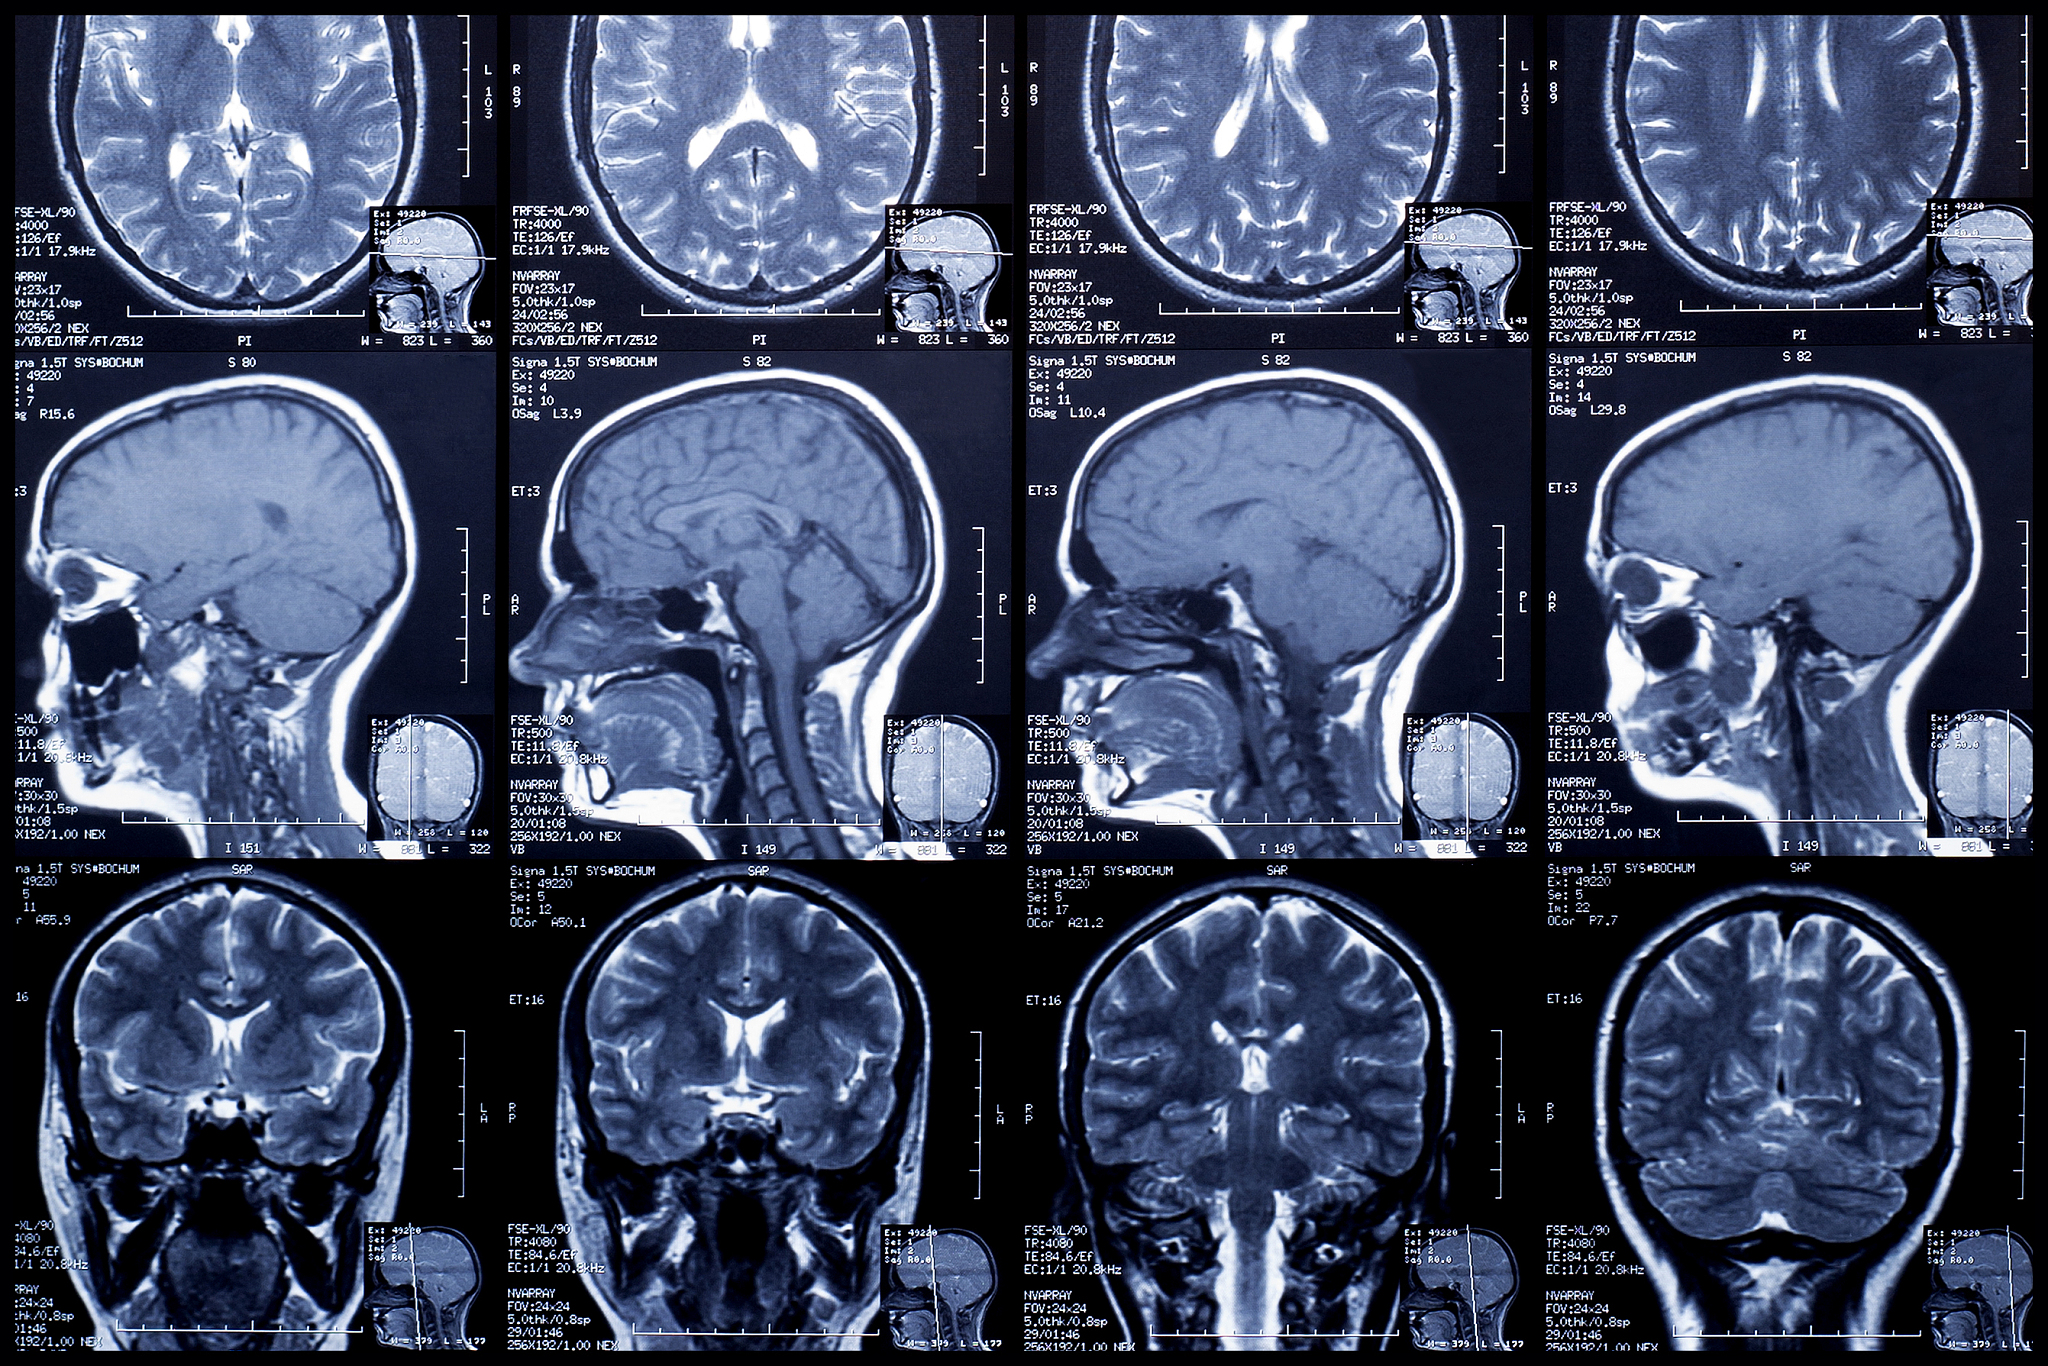

如果您出现了'硬膜囊受压'、'头顶疼'的症状,建议您尽快就医。医生会根据症状和检查结果,制定相应的治疗方案。可能需要进行影像学检查,如MRI或CT等,以确定'硬膜囊受压'的原因。